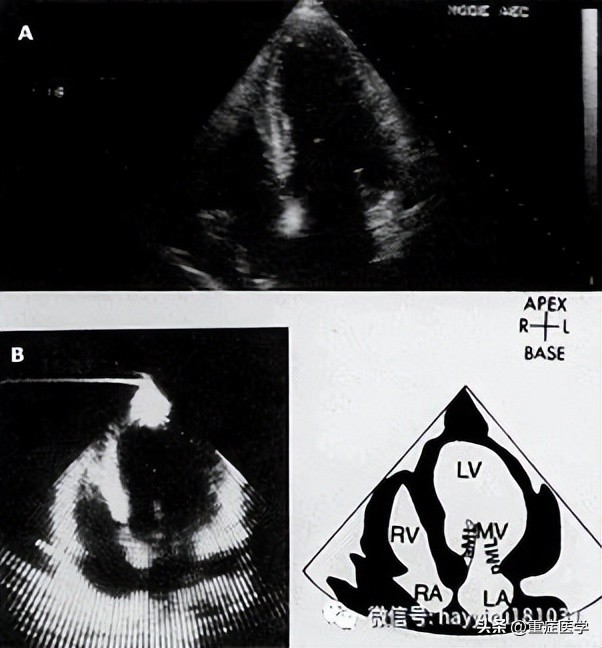

即时超声—POC超声的流程包括休克患者快速超声检查(rapid ultrasound in shock, RUSH)、重点心脏超声(focused cardiac ultrasound, FOCUS)以及休克患者腹部和心脏超声评估(abdominal and cardiac evaluation with sonography in shock, ACES),更常用作不明原因休克和低血压患者的便携式床旁诊断工具。当条件允许时,POC超声通常用于经临床和实验室评估未做出经验性诊断的患者,或进行确定性影像学检查不安全的患者(流程图 1A-B),也用作检查补液效果的辅助工具。虽然POC超声不能确定诊断,但我们认为,当由受过培训人员对有不明原因休克或低血压的危重患者将其作为时效性诊断工具使用时,可获得能挽救生命的有价值信息。多器官超声(RUSH、ACES)首先检查心脏,之后检查胸部、腹部和大血管;FOCUS仅检查心脏。不明原因的休克患者中POC超声采用的技术视图与在创伤患者中使用的(FAST)类似,将单独详细讨论。POC超声检查的组成将在下文简单介绍:首先,应该实施有限视图的心脏检查,查看下列部位:心包–心脏超声可能发现心包积液(无回声带);心腔塌陷,以及呼吸过程中右心室和左心室容积呈相反变化支持心包填塞为休克原因。心脏超声也可用于引导心包穿刺和检查引流效果。左心室–左心室偏大伴收缩力降低可能提示原发性泵衰竭,需要安排适当的干预(如心导管术)。相反,心腔较小和左室高动力可能提示脓毒症导致的分布性休克或血容量不足,分别需要进一步评估脓毒症来源或评估出血。左心室成像也可用于确定安置起搏器(经皮或经静脉)引起的心室收缩或室壁穿孔,或动脉瘤破裂。右心室–右心室收缩力降低可能提示右室心肌梗死;右心室扩大(如,右心室/左心室体积>1:1)可能提示大型肺栓塞或肺动脉高压;右心房/右心室中漂浮的血栓或移动的血凝块也支持肺栓塞。下腔静脉–呼气末下腔静脉(inferior vena cava, IVC)塌陷提示失血性或非失血性原因导致的血容量不足。下腔静脉扩张可能支持心包填塞或肺栓塞。第二,应对胸部和腹部进行简明成像来检查下列部位:肺和胸膜腔–无肺滑行征(视频 5)支持气胸的存在。肺水肿(证据为存在B线)可能支持原发性泵衰竭或继发于液体复苏的容量超负荷。胸膜腔积液(无回声带或分隔)支持脓胸或血胸,并可指导胸膜腔穿刺。腹膜腔–腹膜腔中有大量液体积聚的证据可提示创伤的出血源,或感染的潜在来源(即,肝硬化患者的自发性细菌性腹膜炎)。第三,应对大动脉和静脉进行简明成像以检查下列部位:主动脉–虽然首选胸部CT或经食管超声心动图,但POC超声可发现胸部或腹部动脉瘤或与主动脉夹层相符的内膜瓣。另外,查见游离液体、心包积液或胸膜腔积液也可作为动脉瘤破裂或动脉夹层的间接证据。近端下肢静脉–股静脉缺乏可压缩性可能提示深静脉血栓形成,从而提示临床医生怀疑肺栓塞。如果POC超声不具诊断意义或无法进行,只要条件允许应该进行确定性影像学检查,其中综合性超声心动图最有帮助。同样,如果从休克中成功复苏,采用标准影像学进行后续检查以证实通过快速床旁超声获得的诊断也是明智的。在不明原因的休克患者中,POC超声的优缺点包括: